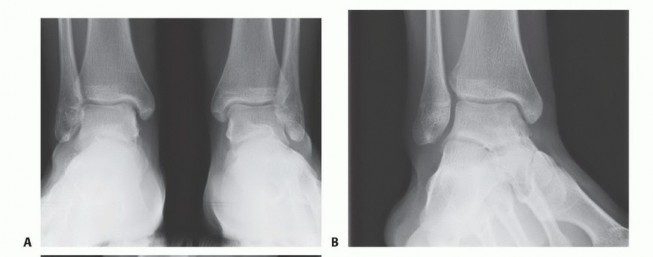

DEFINITION The term osteochondral lesion of the talus (OLT) refers to any pathology of the talar articular ca…

DEFINITION Osteochondral lesion of the talus (OLT) may cause significant pain and mechanical symptoms in the …